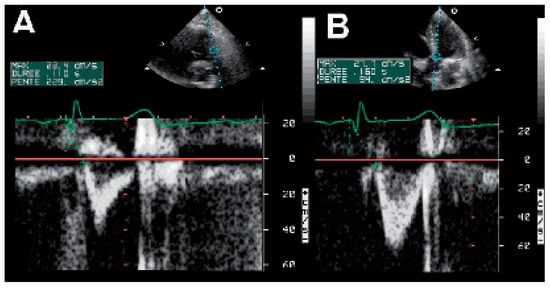

The incidence of heart failure is increasing and patients are threatened to die of pump failure as well as of sudden cardiac death (SCD). Lately, cardiac resynchronisation therapy (CRT) has been introduced to treat patients with persistent heart fail...